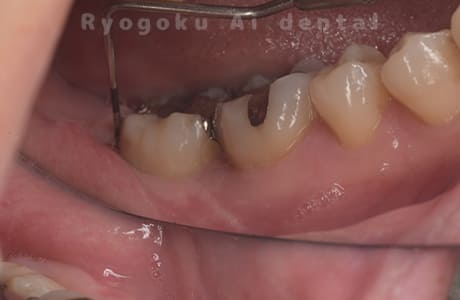

左下からの出血がと違和感があるとのことで転院された患者さんです。衛生士さんとのブラッシング指導、並びに、歯石のお掃除を終えても歯周ポケットの改善がなかったため、再生療法を行いました。歯周ポケットが約8ミリ存在した部分が2ミリに改善し、出血もなくなりました。